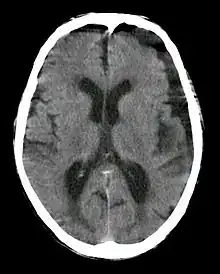

| Subdural hygroma, frontal and temporal. Man of 80 years old. | |

In CT scan, subdural hygroma will have same density as the normal CSF. Meanwhile, in MRI, subdural hygroma will have same intensity with CSF. If iodinated contrast is administered during CT scan, the hygroma will produce high density because of the contrast at 120 kVp. However, at 190 kVp, hygroma with contrast will have intermediate density.[2]